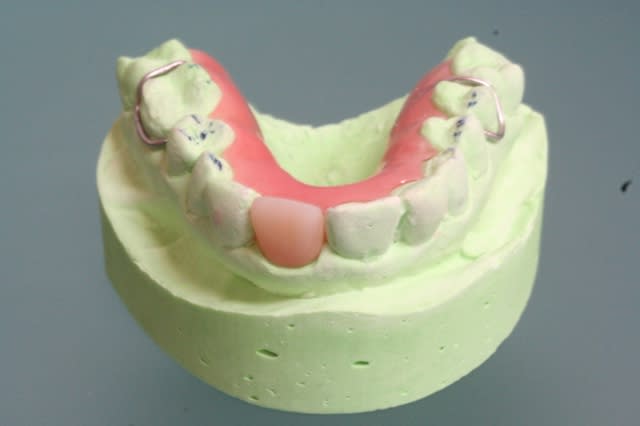

fracture d'une racine 21, infection vestibulaire

1 vue clinique

2 provisoire réalisée avec empreinte de la patiente en ayant retiré la couronne (histoire d'avoir la forme exacte de la gencive le jour de l'extraction)

3 et 4 fendu = foutu !

5 oups ... même photo.

6 RTR en place mais extraction du pan vestibulaire seulement pour avoir un site non infecté et une gencive cicatrisée (donc plus facile à suturée)le jour de la pose de l'implant.

7 dent provisoire maintenant la gencive en place.

ma question;

auriez vous extrait la dent dans sa totalité tout de suite en implantant immédiatement avec les risques infectieux? ou alors extraction, cicatrisation (et donc perte du volume gingivale) puis implantation?